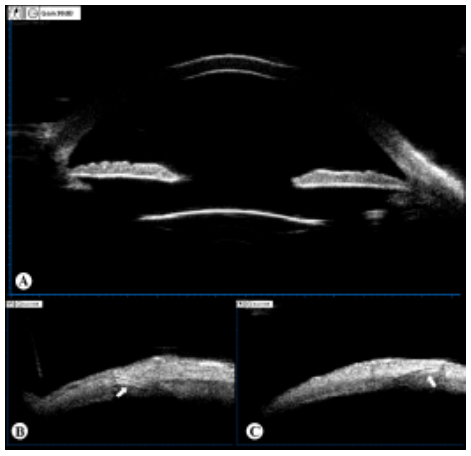

患者,男性,73岁,“左眼因外伤行晶状体摘除术后4月余”于2019年07月22日就诊,拟行二期IOL植入术。入院前4月余,患者因左眼钝伤导致“左眼晶状体半脱位、左眼视网膜脱离”在我院行“左眼玻璃体切除+脱位晶状体切除+视网膜脱离修复术”,术后视网膜伏贴良好。无特殊既往病史。入院诊断为:1)左眼无晶体眼;2)左眼视网膜脱离修复术后。入院检查:VOD 1.0,VOS 0.02,矫正视力1.0(+9.50 DS/-1.25DC×90°),双眼眼压正常。右眼未见异常;左眼角膜透明,瞳孔圆,直径约4 mm,虹膜震颤,晶状体缺如;散瞳检查:无晶状体囊膜残留,视网膜贴伏。左眼眼轴长度23.56 mm,角膜内皮细胞密度为1684.3 /mm2。顺利行 “左眼改良YAMANE式后房型IOL巩膜固定术”[Sensar AR40(Johnson & Johnson),22.0 D,SRK/T公式,预留目标屈光度?0.33D]。术后第一天,裸眼视力 0.7,眼压 11.9 mmHg(1 mmHg=0.133kPa),IOL位正。术后5个月,裸眼视力0.8,矫正视力0.9(+0.50 DS/-1.50 DC×90°),眼压 13.3mmHg,角膜内皮细胞密度 1644.4 /mm2;IOL位正(图1A),其襻在巩膜层间固定良好(图1B~C)。随访期间视力稳定,无IOL移位、偏心、脱位及襻暴露等并发症。

图 1 改良 YAMANE 式后房型 IOL 植入术后

(A) 超声生物显微镜检查 IOL 在眼内位正,无明显倾斜;(B~C)

IOL 襻 ( 白色箭头 ) 在巩膜隧道内固定。